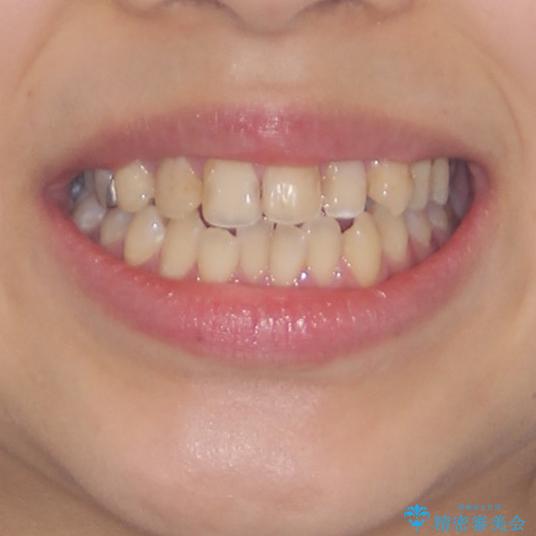

- 中学生の時に矯正治療をしたものの、後戻りを気にして来院された患者様です。

骨格的に下顎が右側に変位しているため、左右の咬み合わせを理想的なものに改善することはできませんが、インビザラインにて歯列を整えることとしました。

骨格的なズレによる左右差は改善できませんでしたが、上下の正中を極力合わせるようにすることができました。